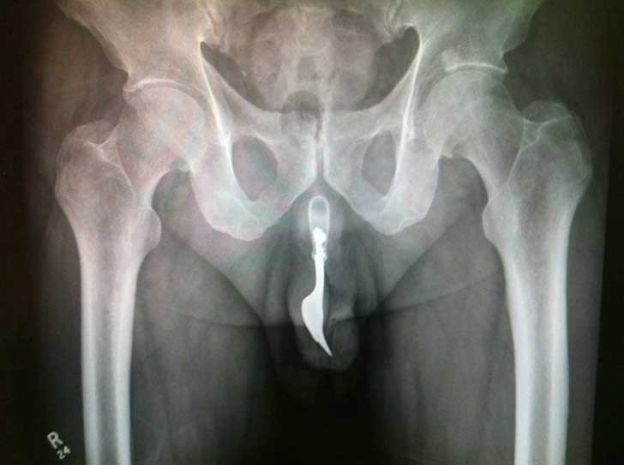

© Reprodução

Garfo